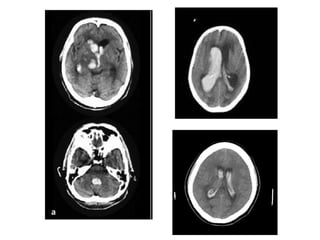

• TC sem contraste 

Deve-se avaliar cuidadosamente as regiões

periventriculares (núcleo caudado e tálamo em

particular), para excluir que um AVCh tenha rompido em

direção aos ventrículos

4. Diagnóstico

Score Graeb